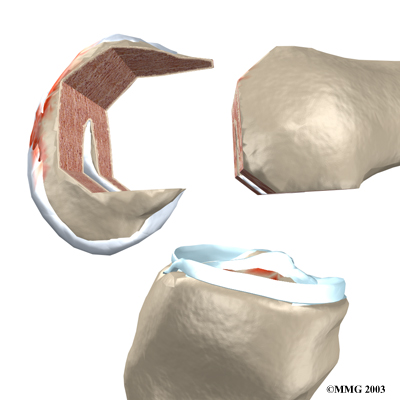

Once the knee joint is opened, a special positioning device (a cutting guide) is placed on the end of the femur.

This cutting guide is used to ensure that the bone is cut in the proper alignment to the leg's original angles, even if the arthritis has made you bowlegged or knock-kneed. With the help of the cutting guide, the surgeon cuts several pieces of bone from the end of the femur.

The artificial knee will replace these worn surfaces with a metal surface.

View animation of removing the joint surfaces: